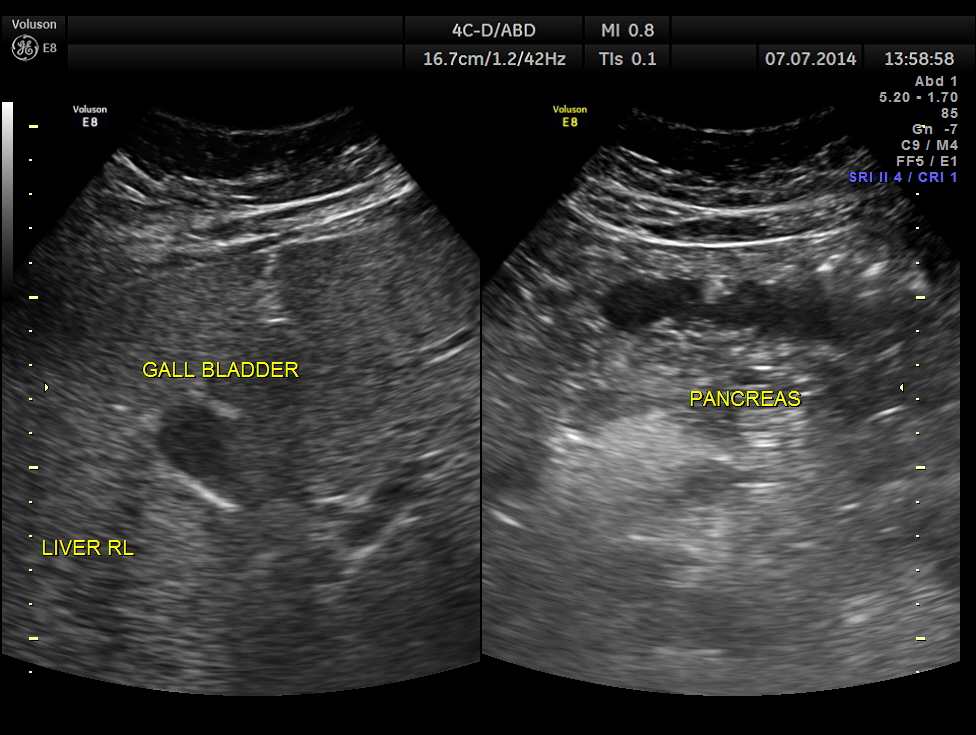

His ultrasound showed the following :